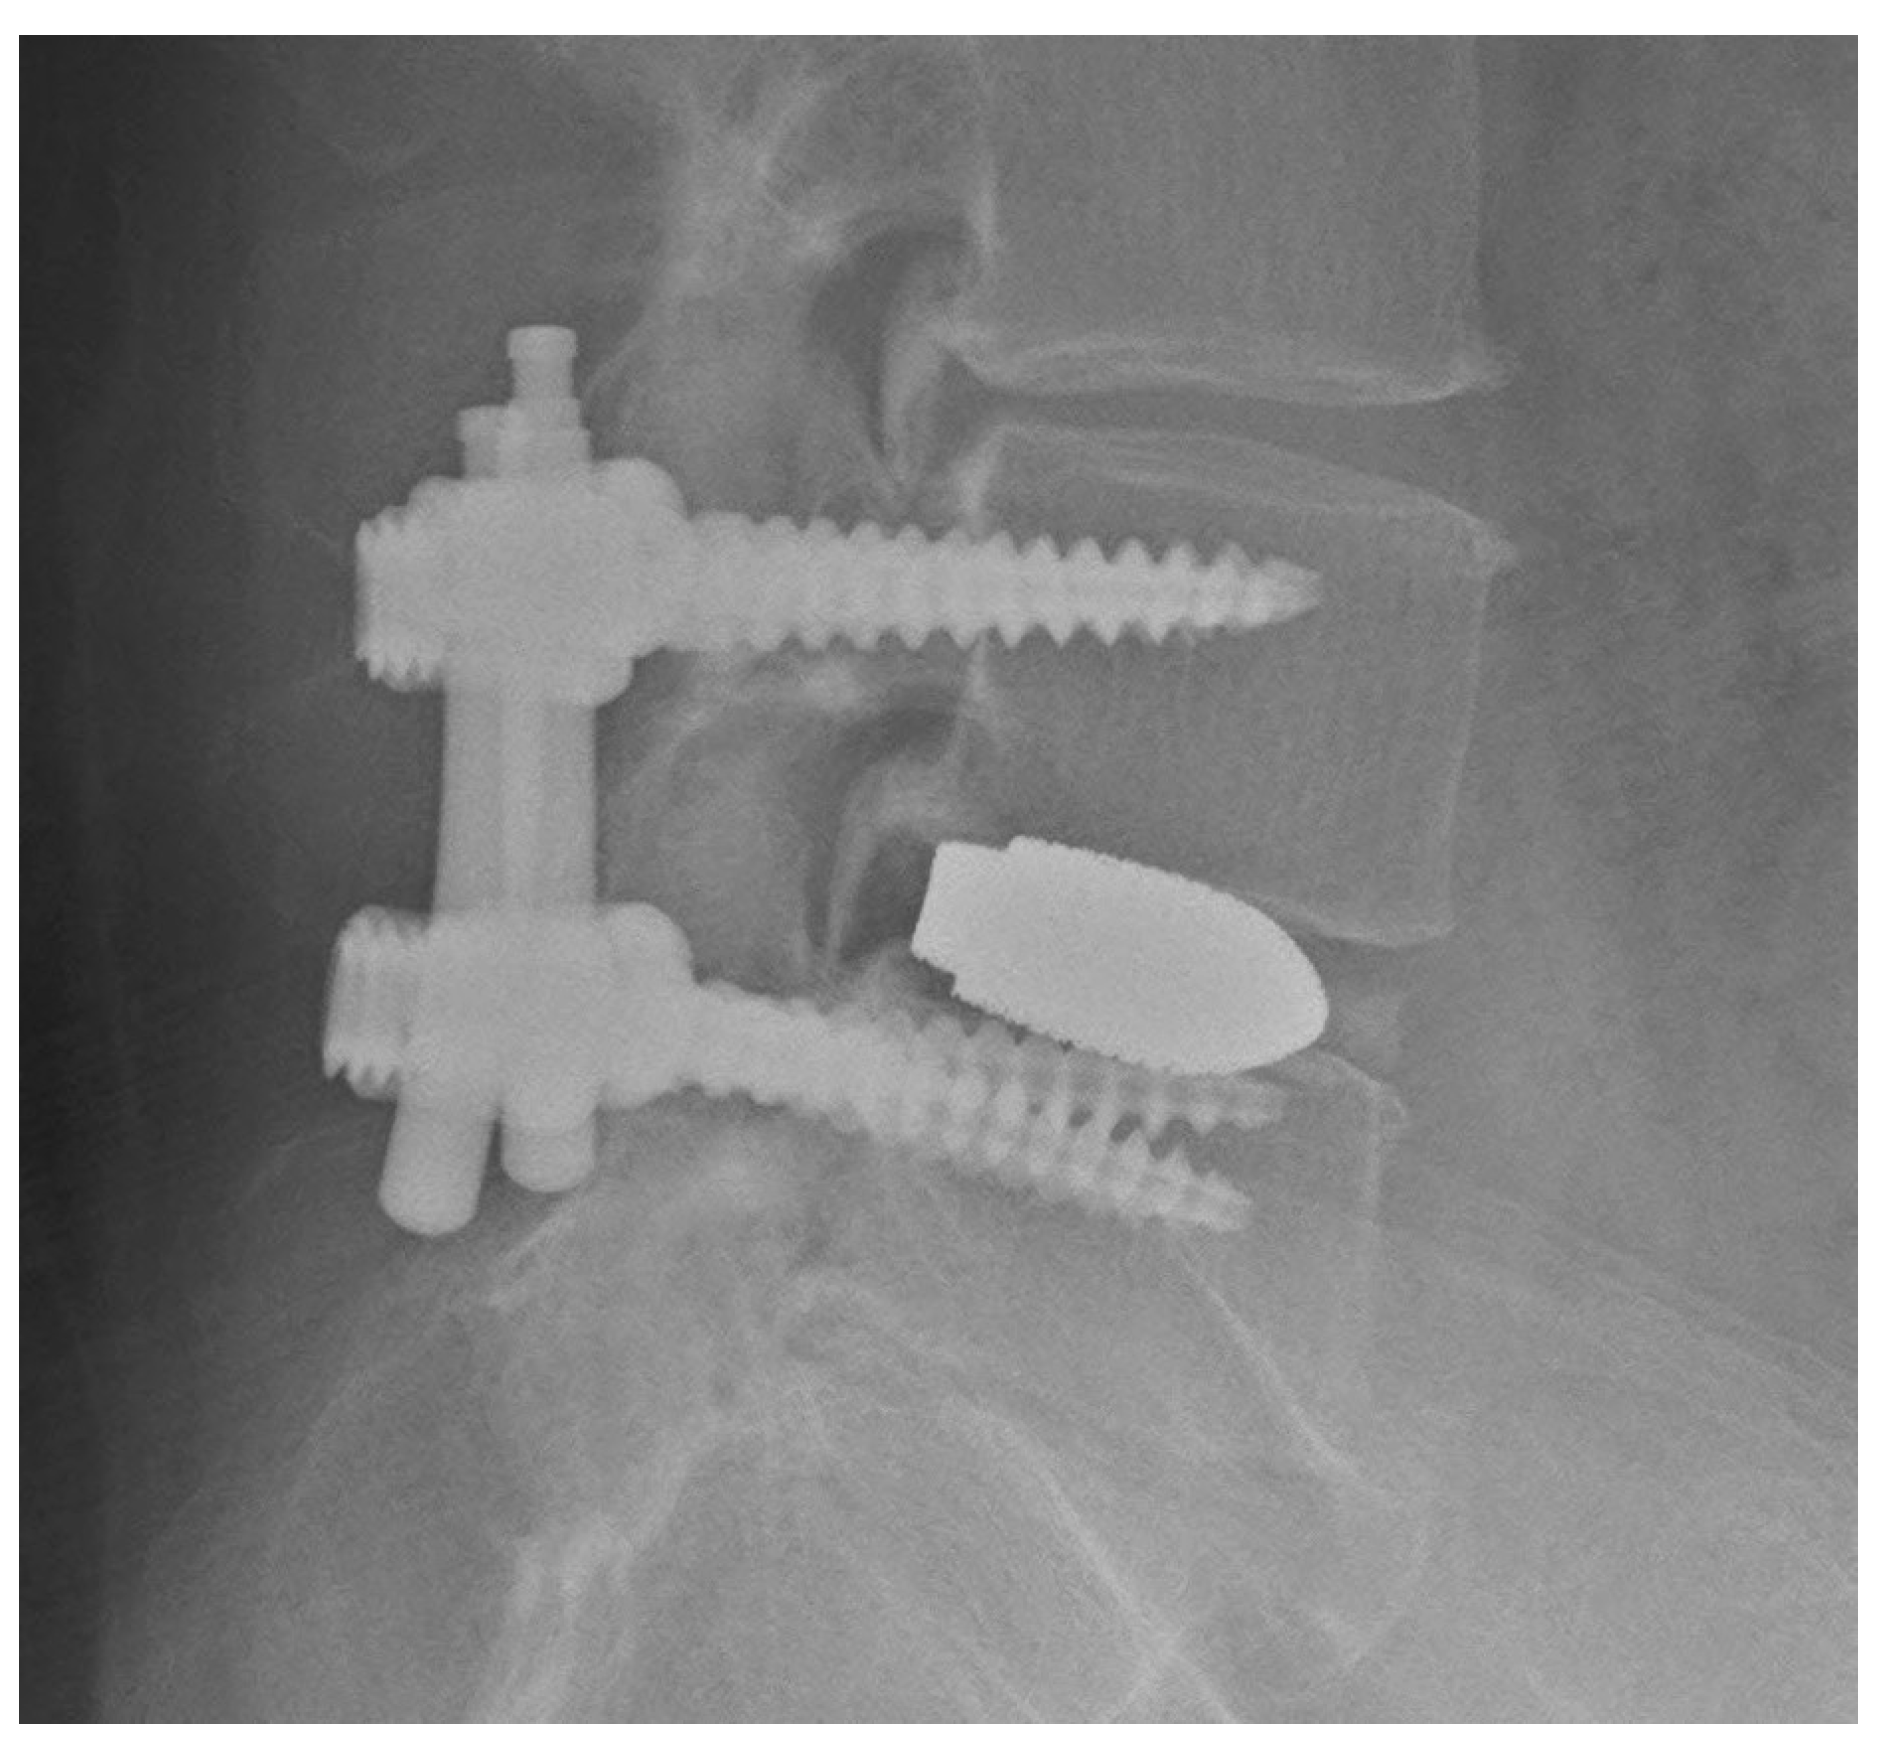

Four self-drilling pins were inserted into the pedicle in the same manner. After confirming the position of the self-drilling pins on a two-way radiograph (Figure 5a), pedicle screws were inserted on the side opposite to the laminectomy using the tubular retractor under a microscope for restoration of disc height (Figure 5b). The length of the pedicle screw was determined using a depth gauge after tapping the inside of the pedicle under the microscope. Self-drilling pins on the laminectomy side were replaced with small pedicle markers so as not to interfere with laminectomy. If self-drilling pin insertion was difficult during this process, the surgeon and staff left the room, and the direction of the self-drilling pin was confirmed and corrected by one-shot AP fluoroscopy.

Figure 5.

(a) Posteroanterior radiograph showing direction of self-drilling pins; (b) Pedicle screw insertion into the opposite side of the laminectomy via the tubular retractor.

Under the microscope, a laminectomy and complete facetectomy were performed on the symptomatic side using a tubular retractor (22 mm diameter), nerve roots were decompressed, and the disc space was accessed. After restoration of the disc height using distractors and completion of the discectomy, an interbody spacer was inserted into the disc space with autologous bone, artificial bone, and 10 mL of bone marrow fluid. After placement of the interbody, pedicle screws on the laminectomy side (Figure 6a,b) were inserted in the same manner as described, and the rod was fastened. All patients underwent postoperative AP and lateral radiography to evaluate instrumentation after surgery.

Figure 6.

(a,b) Insertion of the pedicle screw under the microscope.